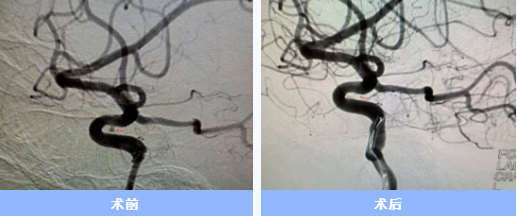

入院后急診完成了頭頸部血管檢查,卻未發(fā)現(xiàn)動脈瘤。神經(jīng)內(nèi)科一病區(qū)負(fù)責(zé)人胡蘇華當(dāng)晚緊急為患者做了更精確的腦血管造影,終于發(fā)現(xiàn)右側(cè)頸內(nèi)動脈上藏著一個極其微小的動脈瘤——直徑僅約1毫米左右,堪稱從醫(yī)二十多年來遇見的最難發(fā)現(xiàn)的"炸彈"。

手術(shù)當(dāng)天,胡蘇華與主治醫(yī)師陳浩協(xié)作,首先經(jīng)患者右手橈動脈成功建立治療通道,隨后才實施全身麻醉,以最大限度縮短麻醉時間。憑借精湛技藝,團(tuán)隊迅速而完整地栓塞了動脈瘤。術(shù)后患者很快在ICU蘇醒,四肢活動良好,第二天即返回普通病房。